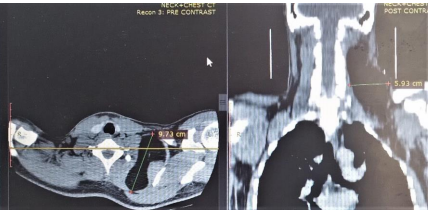

The computed tomogram of the neck showed a hypodense (HU = -109) mass demonstrated in the left paraspinal space of the neck extending from the level of C2 to T1 vertebrae and from posterior to anterior aspect of the neck. It measures about 148 x 97 x 59 mm in its widest craniocaudal, antero-posterior and transverse dimensions respectively (figure, 1 and 2). It shows well outline margin and thin internal septae. There is some enhancement of the septae and the margin of the mass in the post contrast series. No calcification was demonstrated within the mass. There is displacing the adjacent muscles. Anterior displacement of the internal jugular vein and common carotid artery was noted. No intrathoracic extension is demonstrated. No lymphadenopathy is demonstrated. A diagnosis of giant left side neck (paraspinal space) lipoma was made.

Figure 2: Computed tomogram of the neck axial and coronal planes showing a fat density mass (lipo

The benign lipomas are the most common of all mesenchymal tumours [2]. They may be located in all parts of the body and may be classified anatomically as superficial or deep [2]. Most of the head and neck lipomas are superficial and are found in the posterior region of the neck. Deep neck lipomas are rare [2]. The index case is a deep lipoma located predominantly in the posterior aspect of the neck and extends to the anterior region (figure. 2). A Giant lipoma is when a lipoma grows to a size of atleast 10 cm in one dimension or weighs a minimum of about 1000 g as demonstrated in this case (figure 1). Lipomas may occur sporadically or as part of an inherited disease such as familial multiple lipomatosis [5]. They may also occur secondary to trauma with rupture of the fibrous septae inducing adipose tissue migration and proliferation [5].

Imaging plays vital role in evaluation of lipoma. Diagnostic imaging employed, include ultrasonography, plain radiography, computed tomography (CT) scan or magnetic resonance imaging (MRI). The cross sectional imaging (CT and MRI) though not readily available has the advantage of assessing the exact location, size and relationship with surrounding structure. [1,2]. They can also help in differentiating benign lipomas from malignant lipomas. On imaging lipomas are well-defined mass of mature fat (adipocytes) and appears as radiolucent on radiographs, low attenuation on CT with Hounsfield Unit (HU) of -65 to -120 (fig, 1 and 2) and hyperintense on T1-weighted MRI. Fine septations can be seen on both CT and MRI. Features that suggest malignancy include thick capsule, ill-defined border, thick or nodular septations, prominent areas of high T2 signal on MRI and prominent areas of enhancement in the post contrast phase [1,2].